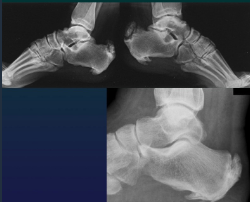

Enthesopathy AS = spicules, brush

Tendon insetion

Iliac crest

Grater trochanter

Ischiatic tubeerosity

Calcanean enthesitis

Septic Arthritis Rx

Normal Rx

Intraarticular effusion

Periarticular OP

Joint space narrowing

Blurred cortical bone

Subcondral bone destruction

Erosion + osteomyelitis

Ankylosis (rare)